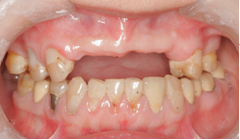

2、龋病

老年朋友根面龋比较常见。龋病在最初的时候往往没有什么症状,出现疼痛就诊时可能已经需要行去神经根管治疗了。而很多患者朋友却不在意,任龋患发展,待到就诊时牙齿很多时候都需要拔除了。治疗龋病的策略是早发现早治疗。病情进展到需要根管治疗后往往还需要修复科行冠修复,时间和经济都是种损失。而任龋病进展到需要拔牙的程度就得不偿失了。